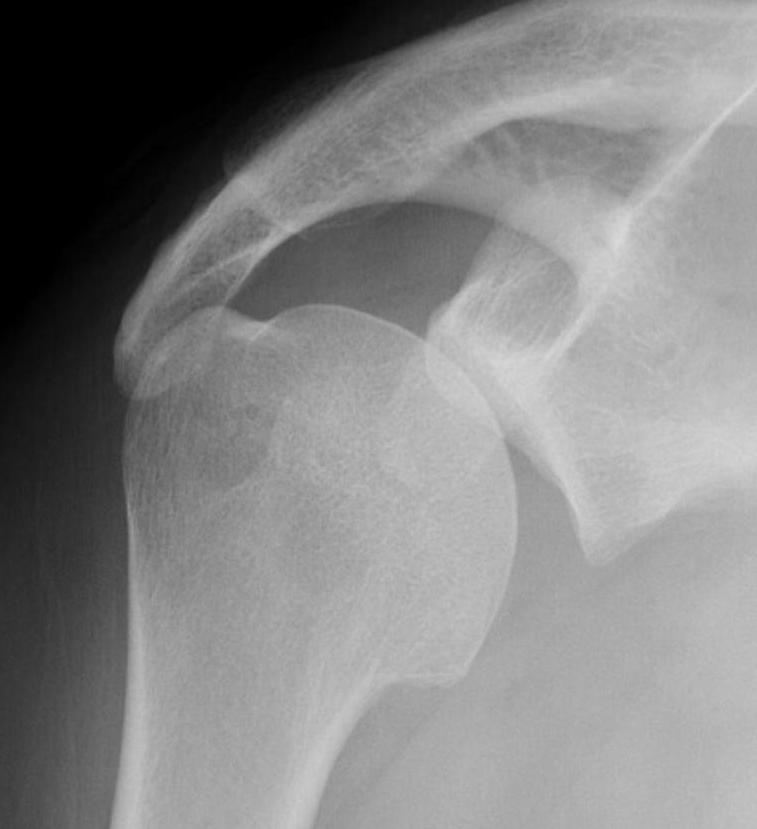

Scapular lateral

Center of the humeral head must be centered on the Y / Mercedes sign

Y is formed by

- coracoid anteriorly

- scapular spine posteriorly

- scapula body inferiorly

Normal scapular lateral